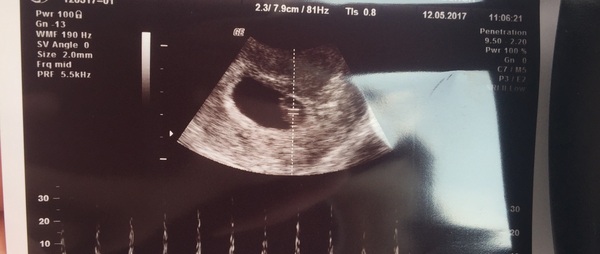

biginjapan · 12/05/2017 11:14

Had my first dreaded internal - here it is - such a relief not to be posting crappy lines on an ic and a proper baby instead.

Congratulations Japan that's a lovely little pic x

Lovely pic Japan Smile

Great pic Japan!

Great scan Japan

Oh Japan Smile I'm so happy for you!

Awwww Japan! So happy for you 😊